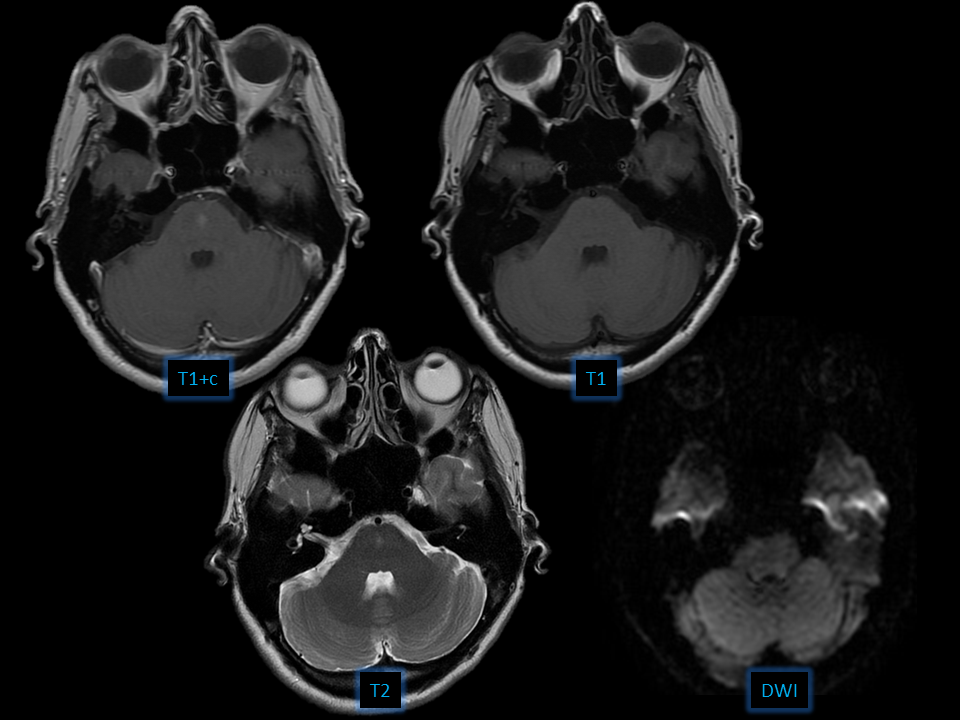

- Central pontine enhancing focus

- No mass effect

- Capillary telangiectasia

- Developmental venous anomaly

- Metastasis

- Cavernous malformation

Brain capillary telangiectasia

• Cluster of enlarged capillaries with interspersed parenchyma

• Enhancement without mass effect

• 50% T2 hyperintense

• Common locations

-Pons

-Cerebellum

-Spinal cord